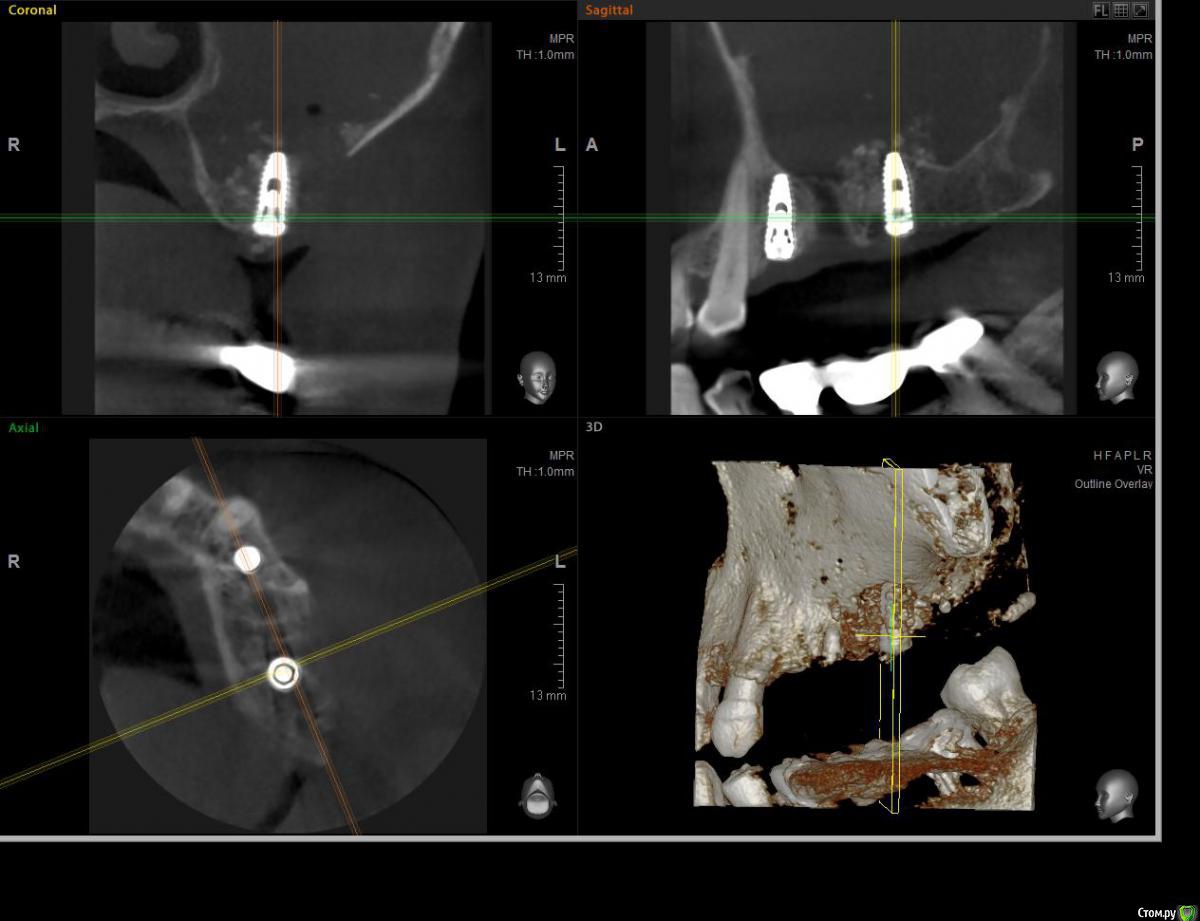

ossa-rr Опубликовано 12 июня, 2017 Поделиться Опубликовано 12 июня, 2017 (изменено) Коллеги, прошу помощи! В конце апреля установил два импланта 24 и 26. В области 26 с открытым синусом. Операция без осложнений, без перфорации и пр. Снял швы через 10 дней. Через месяц пациентка позвонила, сказала, что припухла. Явилась с клиникой периостита в области окна. Вскрыл , установил дренаж на сутки. Есть ли надежда или открывать и убирать все? И еще вопрос по перфорации на кт - как считаете, могла ли она возникнуть как следствие гнойного расплавления или все-таки непосредственно при синус - лифте?Скрины повторного кт : Изменено 12 июня, 2017 пользователем ossa-rr Ссылка на комментарий

Bier Опубликовано 12 июня, 2017 Поделиться Опубликовано 12 июня, 2017 Подключайте ЛОРа, там вся пазуха в гною. 1 Ссылка на комментарий

ПалСаныч Опубликовано 13 июня, 2017 Автор Поделиться Опубликовано 13 июня, 2017 по моему мнению перфорация есть, ибо графт разлетелся по пазухе. Думаю нужно все убрать из места подсадки, пазуху пропунктировать пару раз у ЛОРа, антибиотики, сосудосуживающие. И через месяца 2 контроль КЛТ. Ссылка на комментарий